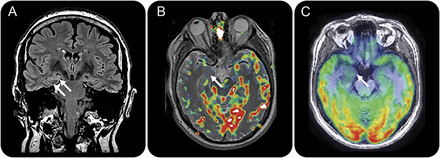

图1

神经影像学自主癫痫持续状态的治疗之前由于anti-LGI1脑炎

在疾病的急性期,日冕fluid-attenuated反转恢复序列(一个)显示hyperintensity正确的海马和杏仁核(箭头),而动脉自旋标记(B)和18F-FDG-PET (C)描述标记hyperperfusion /代谢亢进限制只有这两个结构(箭头),被高度重复发作引起的。